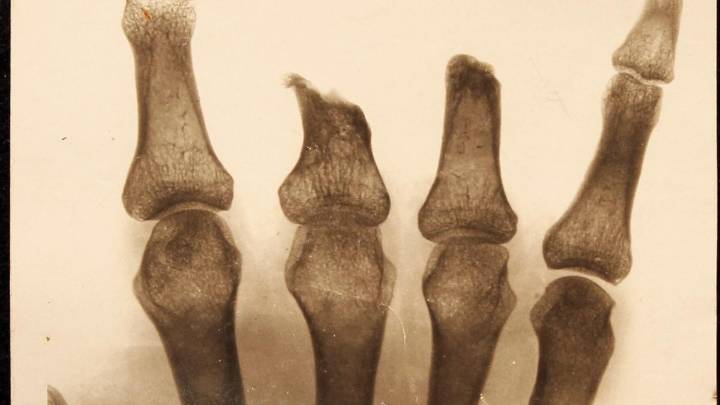

The case of a nine-year-old girl in Kerala who lost her hand after alleged lapses in hospital care has once again spotlighted a troubling issue: many amputations in India are not inevitable, but occur because fractures and wounds are not treated promptly or adequately. Doctors explain how neglect, systemic gaps and lack of awareness create conditions where preventable infections escalate to limb loss.

The earliest hours after a fracture or traumatic wound determine whether a patient heals or risks losing a limb. Navaladi Shankar, senior consultant, orthopaedics at Apollo Hospitals, Chennai, stresses that untreated fractures create the perfect environment for infection.

“The haematoma at the fracture site forms a good culture medium for bacteria. If deb